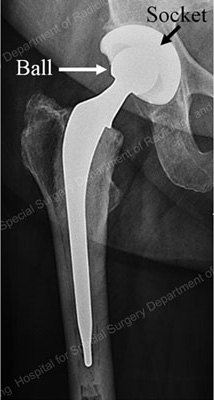

Conventional, primary total hip replacement is a durable operation in majority of patients. A hip replacement is a mechanical device with parts, most commonly referred to as a “ ball and socket,” that are assembled before and during the operation. After surgery, this ball-and-socket prosthesis restores movement in the hip throughout the life-span of the prosthesis (Figure 1).

Figure 1: X-ray of a total hip replacement prosthesis